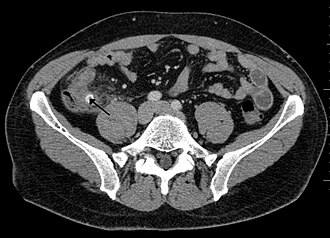

Računalna tomografija

CT abdomena je jedna od boljih dijagnostičkih metoda koja prikazuje prošireni crvuljak sa znacima okolne upale što predstavlja jedan od sigurnih znakova akutnog apendicitisa.